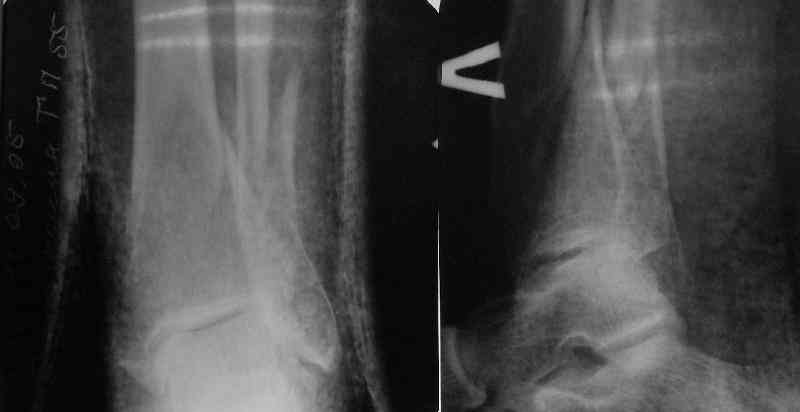

Very interesting application, but is the final position in a little distal varus with some fibula

distraction? Would that have been eliminated by fibula plating?

At least both the ankle mortise and tibial alignment look acceptable, don't they?

I am just trying to illustrate that prevention of 1)tibial valgus and 2)loss of reduction can be provided without fibular plating. Small changes of conventional nailing techniques allow to maintain reduction of the tibia reliably without adjunctive fibular stabilization.

In delayed cases acute length restoration performed only in the tibia may leave the fibula shortened thus change the mortise. So it is reasonable to restore length of both bones simultaneously by distractor and fix the fibula not with open reduction and plating but just by a single perQ screw. Example attached.